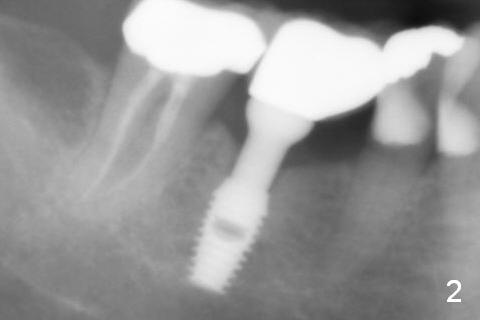

A 74-year-old woman with history of osteoporosis treatment had panoramic X-ray taken 7.5 years post cementation (Fig.2), eight years post Bicon implant placement (Fig.1). Bone density increases around the implant 9 years 7 months post cementation (Fig.3).